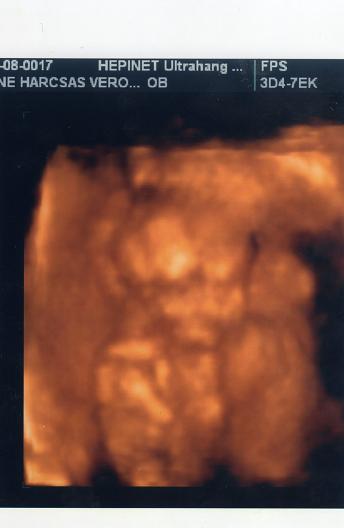

mi ma megyunk itt uh-ra. ez az elso hivatalos uh-m. fogalmam sincs, hogy milyen vizsgalatokat csinalnak. majd irok beszamolot, ha hazajottunk, meg felteszem a kepet. asszem itt az is kiderul, hogy tenyleg dec 15-re leszek e kiirva.